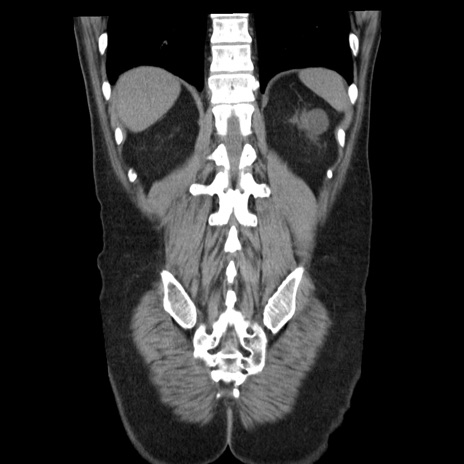

症例29(冠状断像)

【症例】40歳代男性

【現病歴】2日前から胃痛あり。徐々に周期的な激痛に変化した。本日になっても激痛があるため受診。

【身体所見】意識清明、BT 38-39℃台あり、腹部:膨満、やや硬、右下腹部に圧痛あり。

【データ】WBC 8500、CRP 23.26